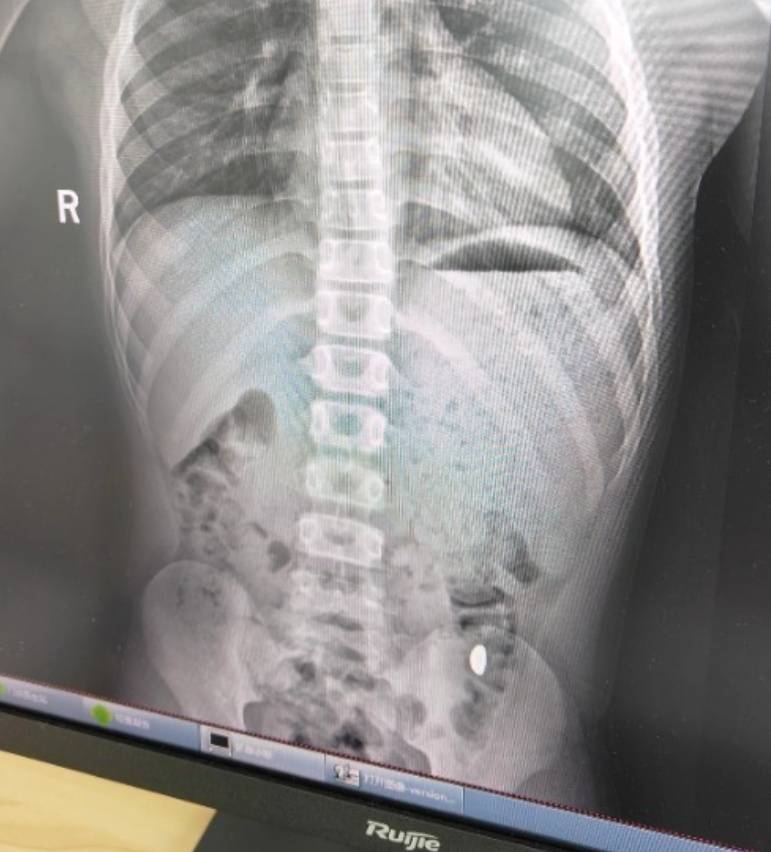

右下加亮点为金豆。